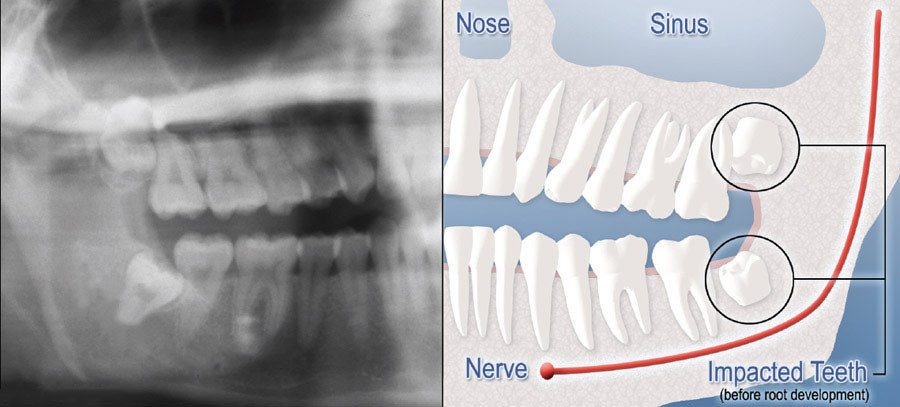

Wisdom Teeth Impaction

We will need to see you for a consultation to determine if you will benefit from wisdom tooth removal. A special x-ray of your mouth and jaws (panorex) will be taken to determine if your wisdom teeth are impacted, if there is room for them to erupt, and how difficult it will be to have them removed.